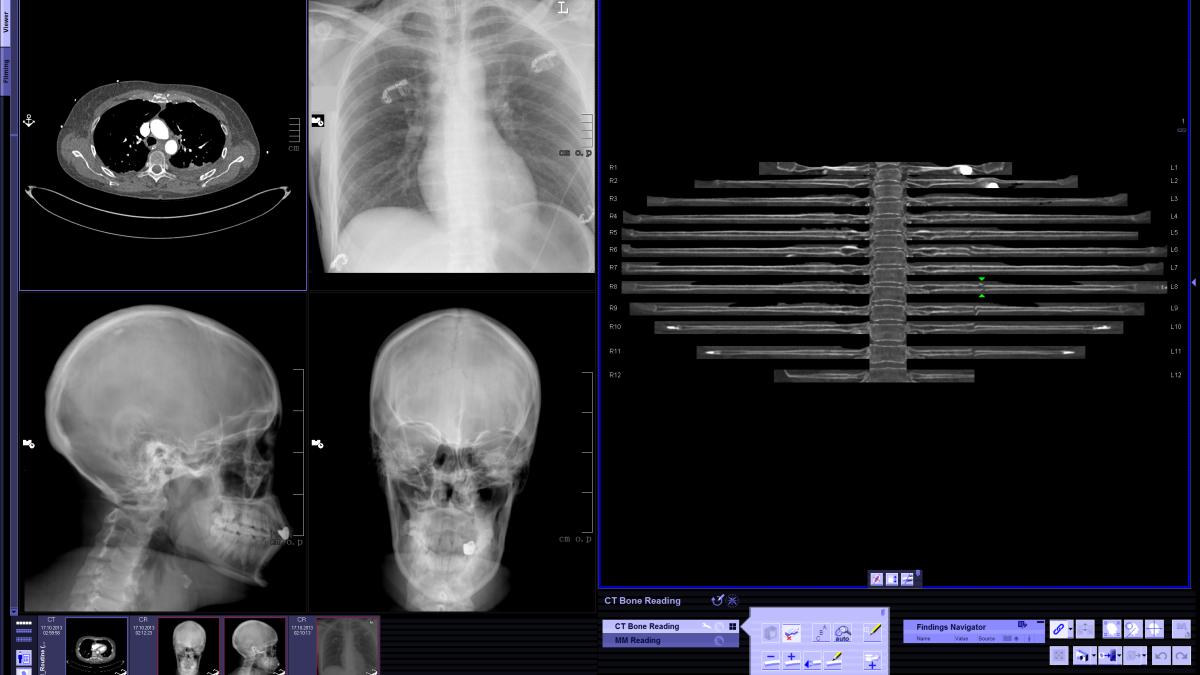

Computerul rezolvă criza de medici radiologi

Pentru a rezolva această problemă, cercetătorii firmei Siemens au pus la punct un soft de prelucrare a imaginilor radiologice care permite creșterea vitezei de interpretare a rezultatelor cu 75%. Programul Syngo.via simplifică munca radiologilor și îi ajută să prelucreze mai rapid datele, iar pachetul de aplicații software  Sygno.via General Engine asigură un nivel ridicat de automatizare și standardizare. Imaginea este prelucrată și recompusă fie 3D, fie 2D.

De exemplu, softul este capabil să identifice regiunile corpului care trebuie scanate și să analizeze rezultatele, ajutând medicul să structureze raportul diagnostic. Radiologii aveau nevoie de un astfel de ajutor mai ales în condițiile în care lucrează cu aparate moderne, care achiziționează până la 200 de imagini pe secundă. Acest volum imens de date trebuie analizat, ceea ce face ca, fără un sistem automatizat de evaluare,  interpretarea datelor să dureze prea mult.

Soluțiile pentru telefoanele mobile contribuie, de asemenea, la un diagnostic rapid și precis: medicul de gardă poate fi ajutat, în situații deosebite, de un coleg aflat acasă, care este mobilizat și conectat prin internet la sistemul Syngo.via. Solicitarea opiniei experților, în  cazuri deosebite,  se poate face  la distanță, prin transmiterea imaginilor cu ajutorul aplicațiilor pentru internet.  Sistemul Syngo.via este unul modular, ceea ce înseamnă că poate fi achiziționat  în timp, în funcție de nevoile și bugetele spitalelor sau centrelor de diagnostic.